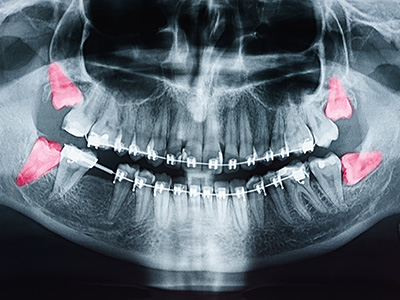

Impactions are often described as soft tissue when covered by gum or bony when covered by bone, and they can be angled toward the neighboring molar, away from it, or lying horizontally. The exact position and relationship to nearby structures are determined with radiographs or CBCT imaging. That detailed view helps clinicians predict potential problems and plan treatment safely.

Evaluation begins with a thorough dental exam and a review of symptoms, followed by imaging such as a panoramic radiograph or cone beam CT when more detail is needed. Imaging shows the tooth’s orientation, depth of impaction, root development and the proximity of important structures like the inferior alveolar nerve and the maxillary sinus. These findings are essential for surgical planning and risk assessment.